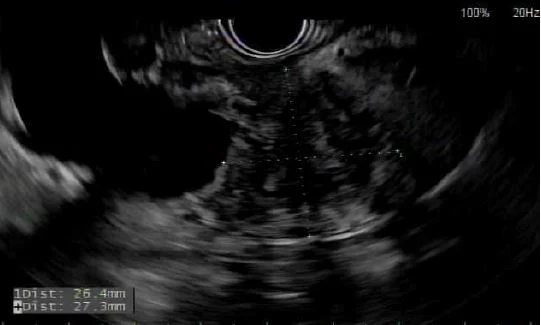

Image from endosopic ultrasound shows hypoechoic mass obstructing common bile duct